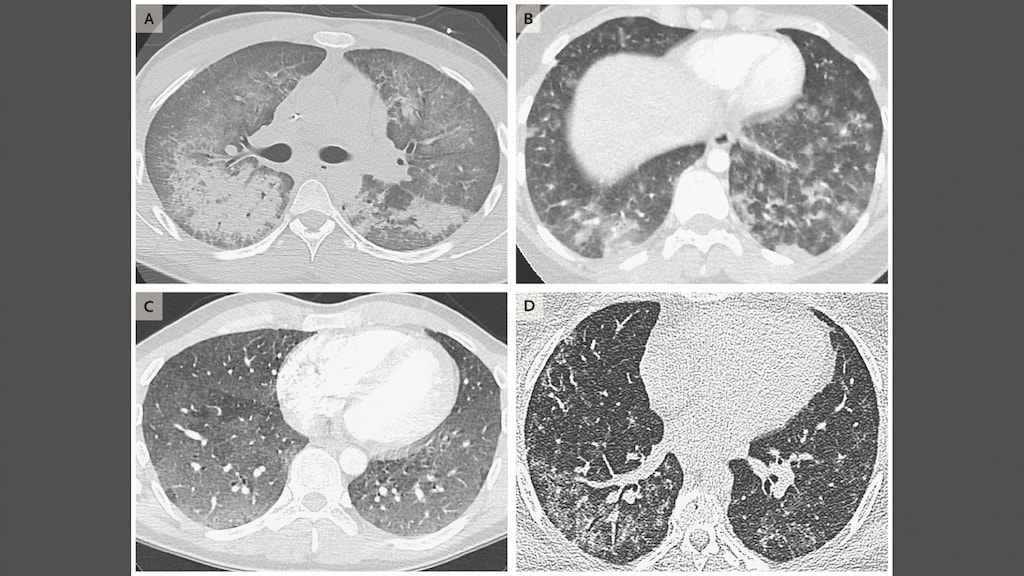

De patiënten kampen met kortademigheid, vermoeidheid, pijn op de borst, hoesten en gewichtsverlies. De overheidsdienst CDC denkt dat de oorzaak van de ziekte een 'chemische stof' uit de e-sigaret is, maar het benadrukt dat het nog niet weet om welke stof het gaat.

Het medisch tijdschrift The New England Journal publiceerde een onderzoek naar 53 longpatiënten uit de staten Wisconsin en Illinois. De patiënten waren bijna allemaal kerngezond voordat ze werden opgenomen in het ziekenhuis en hadden een gemiddelde leeftijd van 19 jaar. De helft van de longpatiënten moest worden opgenomen op de intensive care, een derde had zo veel moeite met ademen dat ze aangesloten moesten worden op de beademing.